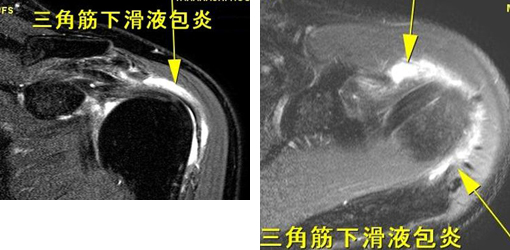

関節のMRI 第3版 | 上谷雅孝, 青木隆敏, 神島 保, 江原 茂, 杉本。肩関節のMRI−読影ポイントと新しい知見−第3版 | 佐志 隆士。その他検査(関節・軟骨) 肩MRI | AIC八重洲クリニック。ホテイ やきとり缶詰 岩下の新生姜入りしょうが味 70g×9缶セット 非常食。【裁断済】\r肩関節のMRI 改訂第3版\r佐志隆士、秋田恵一 編集\rメジカルビュー社\r\r・こちらで購入させて頂いたものです。\r・裁断済みです。そのため、状態は悪いとしています。\r 裁断済みの意味が分かる方のみ、ご購入をお願いいたします。\r・書き込み、マーカーはないと思いますが、確認漏れがあった場合はご容赦ください。\r・スキャン後ですので、多少のヨレやローラー痕がある可能性があります。ご理解の上ご購入をお願いいたします。\r・即購入OKです。\r 恐れ入りますが、値下げ交渉はご遠慮下さい。。肩関節脱臼に対する治療 | 長野整形外科クリニック。その他検査(関節・軟骨) 肩MRI | AIC八重洲クリニック。m3電子書籍 | 関節外科 2022年11月号 Vol.41 No.11 腱板断裂治療。肩関節疾患 | ならやまと整形外科 スポーツクリニック。肩関節(MRI): 正常解剖学 | e-Anatomy。肩関節脱臼|SPORTS MEDICINE LIBRARY|ザムスト(ZAMST)。Open Bore 3T MRIと320列面検出器CTの最新臨床応用 Toshiba 3T。肩関節(MRI): 正常解剖学 | e-Anatomy。プライマリケア医にとってMRIは、確定診断をサポートするための